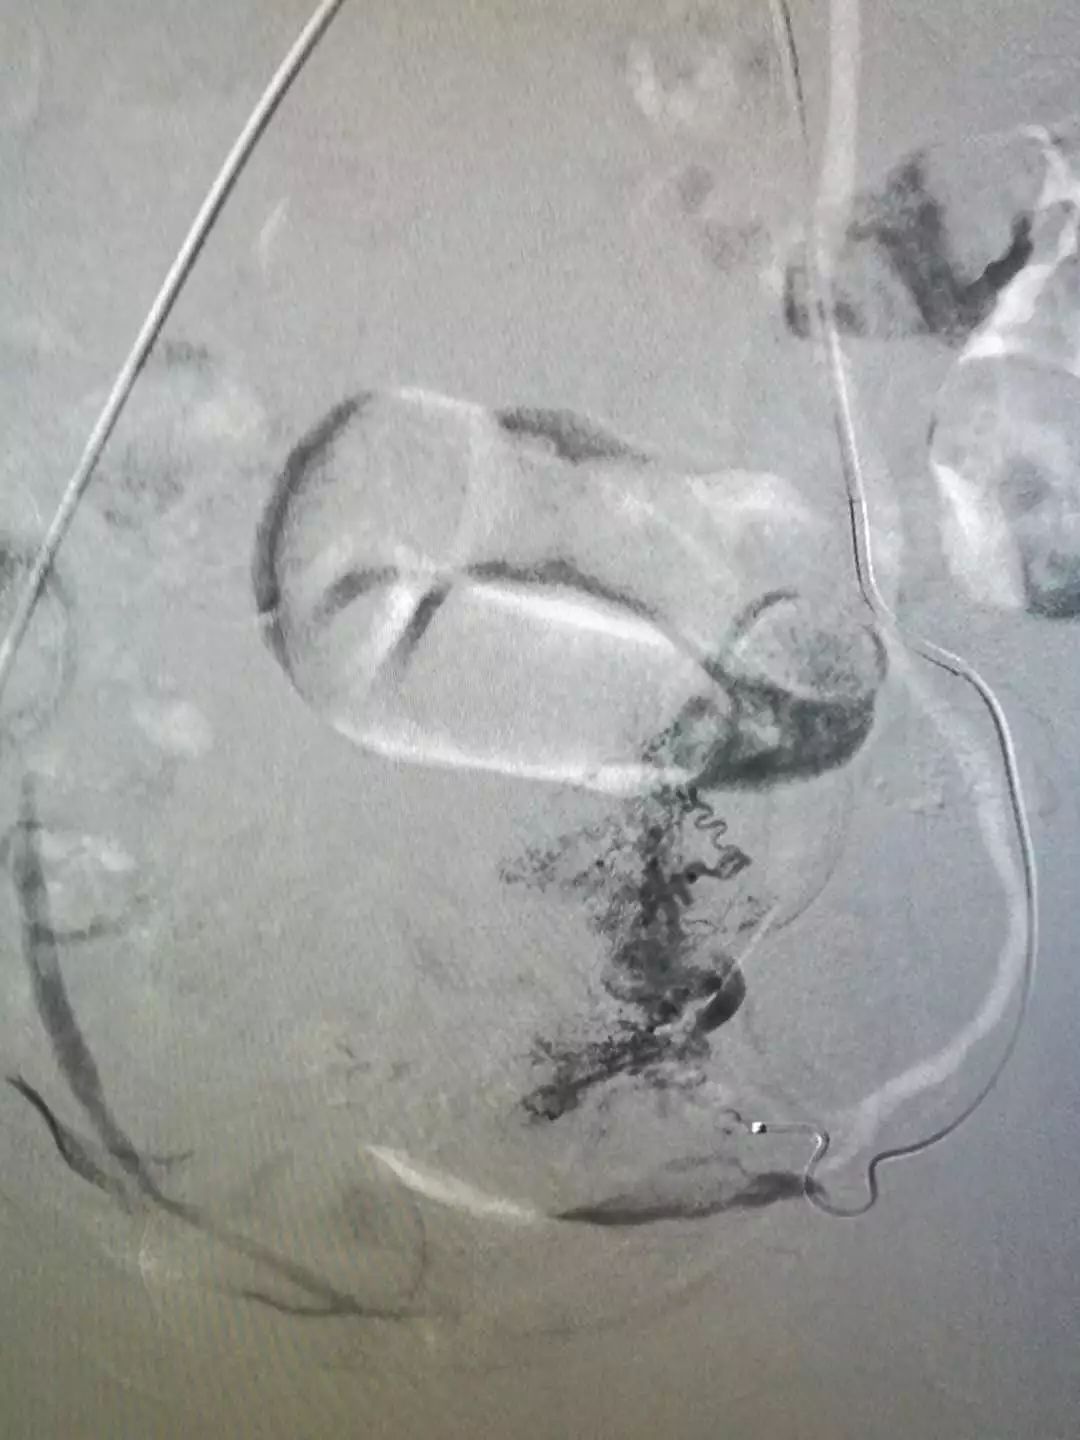

介入栓塞后的碘油沉积

介入栓塞治疗后碘油沉积